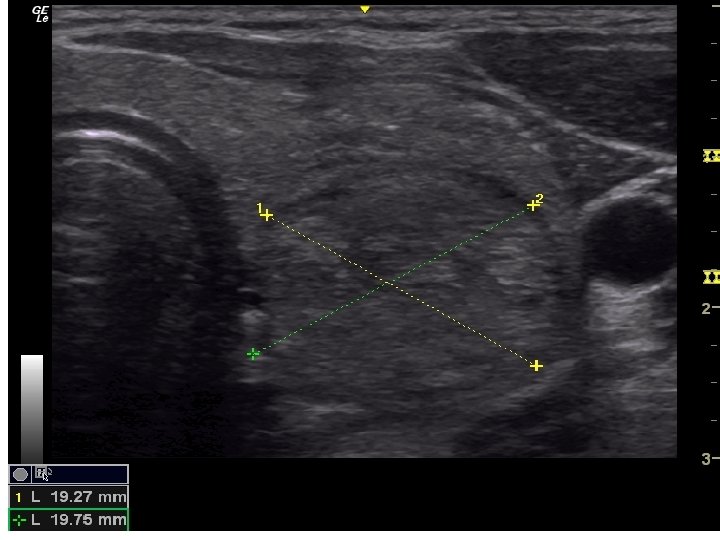

• Tiroid USG • Klinik olarak veya • diğer görüntüleme yöntemlerinde saptanan nodülün tanısının konması için gerçekleştirilir. • USG nodülün – – – – – Boyutu Lokalizasyonu İçeriği Kenar düzeni, Kalsifikasyon varlığı, Ekojenite, Vaskülarite, Şeklinin ve Lenf nodüllerinin değerlendirilmesi için kullanılır.

Sonografik Özellikler, Tahmini Malignite Riski ve İİAB Önerileri Sonografik patern US özellikleri Tahmini Biyopsi için önerilen çap malignite riski >%70 -90 >1 cm Yüksek risk Solid hipoekoik nodül veya solid hipoekoik komponenti bulunan parsiyel kistik nodül: düzensiz sınırlar (infiltratif, mikrolobüle, dikensi), mikrokalsifikasyonlar, boyun enden daha uzun olması, çevrede hipoekoik yumuşak doku komponenti bulunan bozulmuş çevresel kalsifikasyon alanları, tiroid dışına uzanımın kanıtı Orta risk Mikrokalsifikasyon, tiroid dışı uzanım ve uzunlamasına şekil içermeyen düzgün sınırlı hipoekoik solid nodüller %10 -20 >1 cm Düşük risk Mikrokalsifikasyon, tiroid dışı uzanım ve uzunlamasına şekil içermeyen düzgün sınırlı izoekoik/hiperekoik solid nodül veya kenarında uniform solid alanlar içeren kısmen kistik nodül %5 -10 >1. 5 cm Çok düşük risk Ultrasonografik olarak yüksek, orta veya düşük risk tanımlamaları içinde yer almayan spongioform veya kısmen kistik nodüller <%3 >2 cm yapılabilir İİAB yapılmadan izlem de makul bir seçenektir Benign Pür kistik nodüller (Solid komponent yok) <%1 Biyopsi gereksiz( Kist aspirasyonu, semptomlara yönelik veya kozmetik amaçlı planlanabilir. )